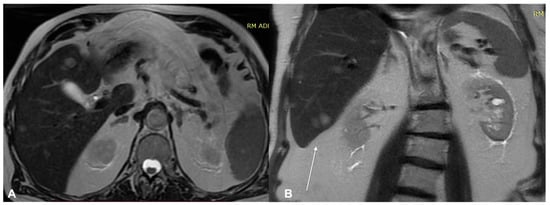

- Granata, V.; Fusco, R.; Piccirillo, M.; Palaia, R.; Petrillo, A.; Lastoria, S.; Izzo, F. Electrochemotherapy in locally advanced pancreatic cancer: Preliminary results. Int. J. Surg. 2015, 18, 230–236. [Google Scholar] [CrossRef] [PubMed]

- Granata, V.; Fusco, R.; Setola, S.V.; Piccirillo, M.; Leongito, M.; Palaia, R.; Granata, F.; Lastoria, S.; Izzo, F.; Petrillo, A. Early radiological assessment of locally advanced pancreatic cancer treated with electrochemotherapy. World J. Gastroenterol. 2017, 23, 4767–4778. [Google Scholar] [CrossRef] [PubMed]